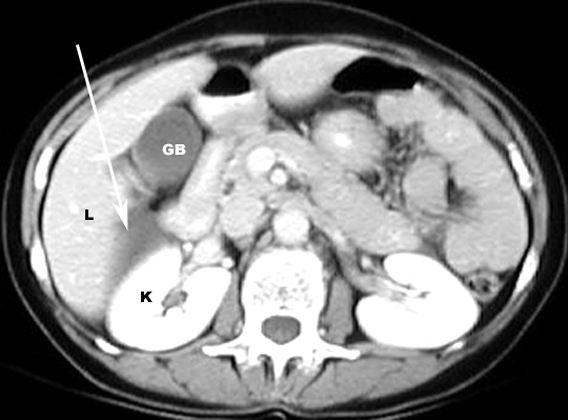

CT: Highly accurate

Signs: